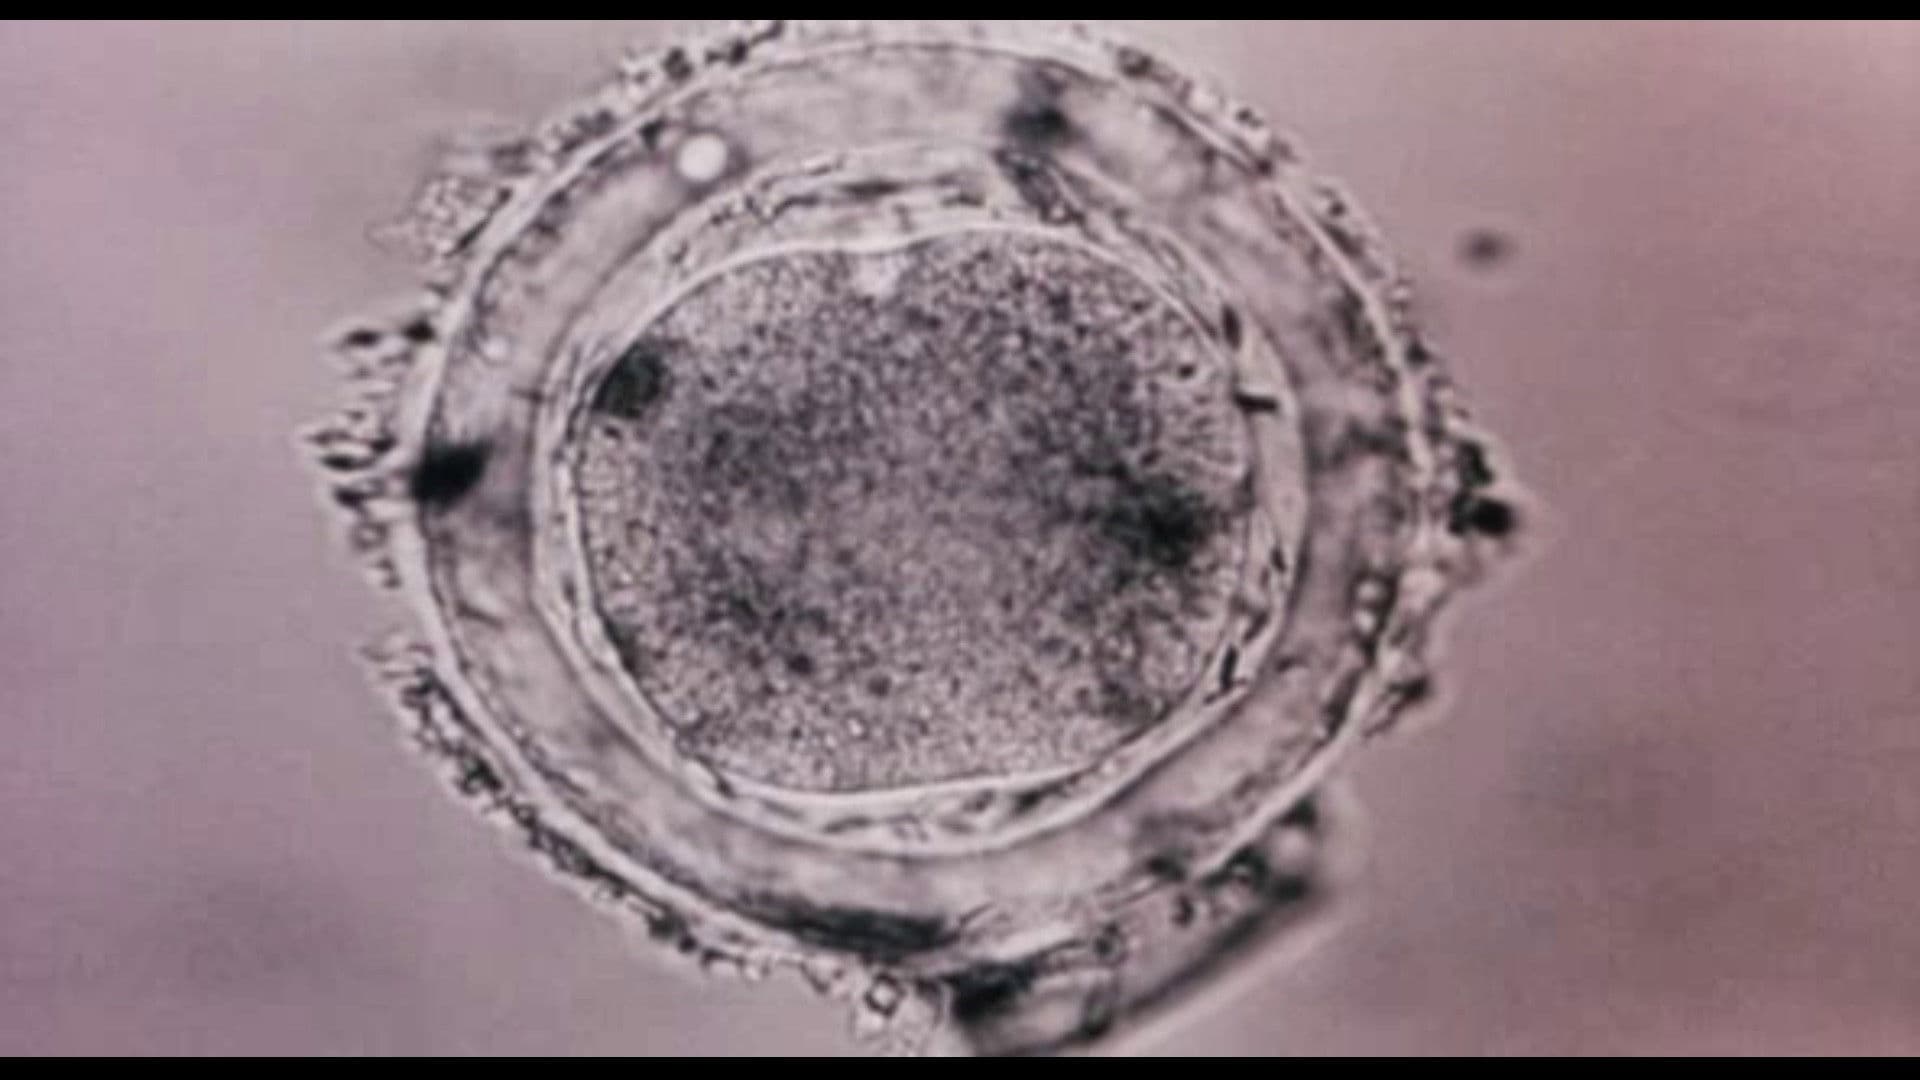

Documentary footage from various sources, set to music. Showing the whole of human life, from birth to death and beyond.